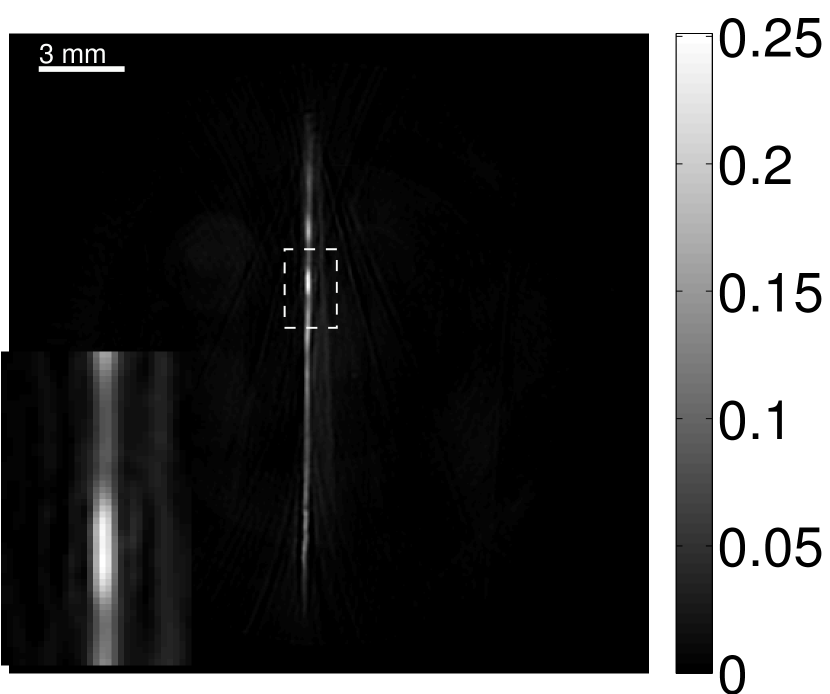

The images and EIRs reconstructed by use of the VP algorithm that was based on the 2D imaging model that neglected the SIR are shown in Figures 15 and 16. The latter figure contains results corresponding to different values for the regularization parameter . From Fig. 15, it can be observed that use of the conventional iterative method that utilized the measured EIR resulted in distortions and loss of details in the reconstructed images. Use of the VP algorithm improved the contrast and the details in the reconstructed images (Fig. 15(c) and 16(a)). Furthermore, the images reconstructed by use of the VP algorithm had a more uniform background.

In Figure 17, the results corresponding to use of the 3D imaging model that incorporated SIR effects are shown. The EIR estimated by the VP algorithm is also shown. In Figure 18, images and EIRs reconstructed by use of the VP algorithm with different regularization parameters values are shown.

Similar to the case described above where the transducer SIR was neglected, these results reveal that use of the VP algorithm can produce images with a cleaner background and enhanced spatial resolution than yielded by use of a conventional iterative algorithm that employed the measured EIR. For example, detailed information regarding the vessels near the organ’s periphery was better preserved by the VP algorithm than by the conventional iterative algorithm. These images corroborate our assertion that the VP algorithm can significantly reduce the artifacts and distortions in the reconstructed image. It is also worth pointing out that, unlike the numerical phantom studies, the artifacts and distortions in the images may be caused not only by the inaccurate EIR but also by other factors, such as neglecting acoustic heterogeneities and the variation of the EIRs among the elements of the transducer array. In such cases, the EIR estimated by the VP algorithm represents an effective system impulse response that minimizes the inconsistency between the measured data and the imaging model.